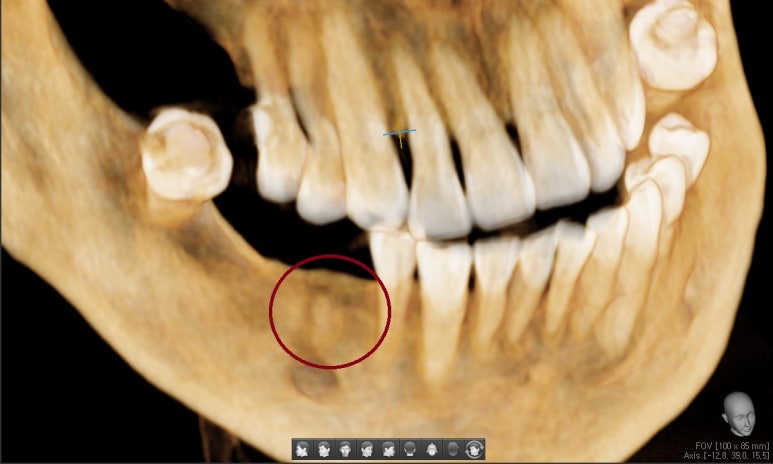

남은 뿌리(완전히 빼기 전)

↑ 저희 시청역 광화문 가까운 치과

연세예감치과의 3차원 치아ct에도

남은 뿌리가 이렇게 보입니다.

무사히 다 빼서 아래와 같이

엑스레이로 확인하였습니다. ↓